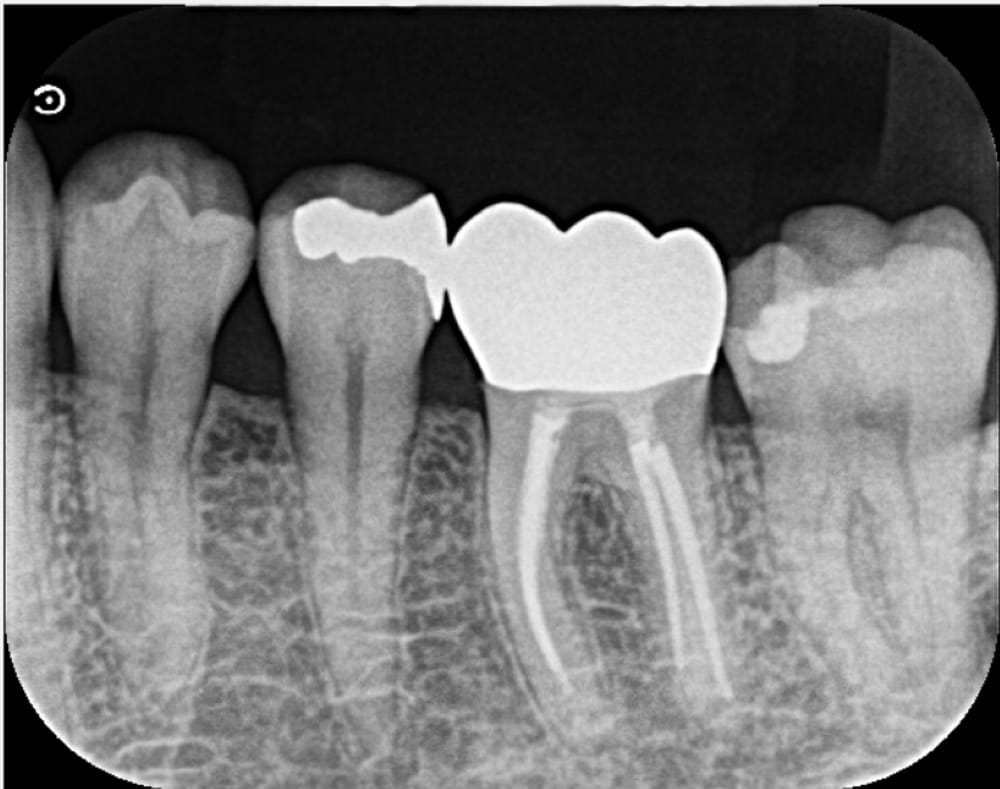

左下6番は仮封がされている状態であり、レントゲン画像では歯と封鎖材料の隙間がある状態でした。口腔内の所見からも、虫歯が残存していることが推測されました。痛みの原因としては、複数回のペリオドンの使用に加え、ラバーダムがない根管治療を受けていることや虫歯が残存していることなどが考えられます。

根管内を徹底的に清掃し、充填のためのガッタパーチャポイントを試適し、根管充填+コア築造まで完了しました。